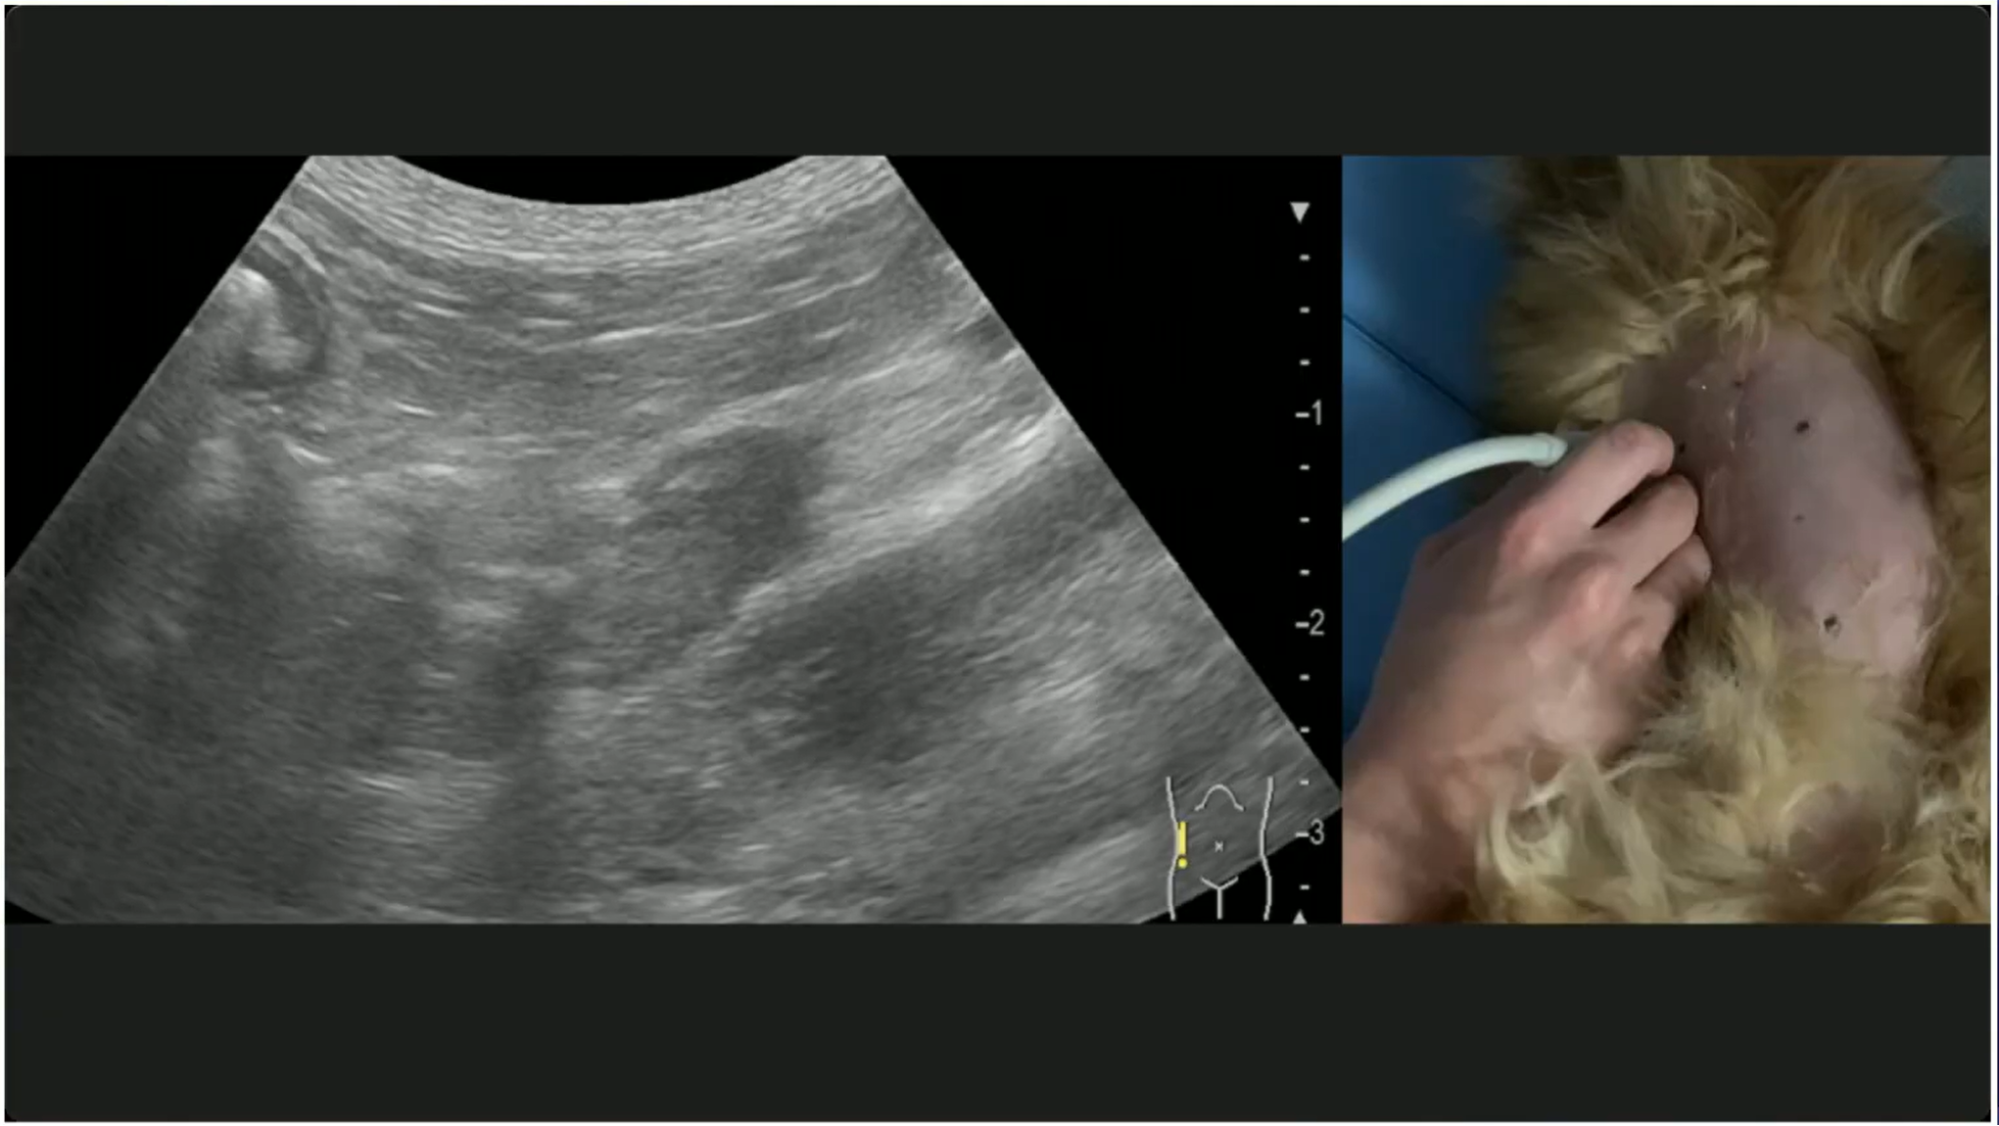

副腎の超音波検査:評価のポイント

血液検査の結果が、決め手に欠ける。そんなときに、診断の補助として非常に有効なのが、エコーによる「形態評価」です。副腎と甲状腺の構造変化を視覚的に捉えられれば、判断に迷う症例にも確信を持って次の一手を選べます。

本教材では、このハードルを乗り越えられるよう、描出手技を「手元の動き+実際の描出画像」の両面から解説。どのプローブを、どの角度で当てれば構造が浮かび上がるのか。永田先生が、臨床で磨き上げた再現性の高い技術を、映像を見ながら習得できます。

さらに、実症例のエコー画像を提示しながら、評価のポイントも丁寧に解説。血液検査の結果と照らし合わせながら、「エコー所見をどう診断フローに組み込むか」を症例ベースで学べます。

ここまで、コンベックスプローブを用いた基本的な副腎の描出方法をご説明しました。ですが、永田先生は「高周波のリニアプローブによる評価が重要である」とおっしゃいます。見え方は、どう変わるのでしょうか?

副腎の評価のポイントと注意点

健康な犬86頭、クッシング症候群の犬91例の副腎を超音波で評価した2021年の論文をご紹介します。副腎の参考基準範囲(健康な大きさ)にはいろいろな報告がありますが、もっとも頭数が多く、新しい報告です。